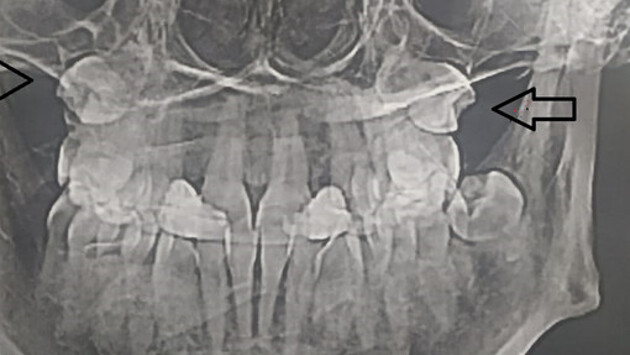

Жительница Самары обнаружила, что в гайморовых пазухах у нее выросли зубы, сообщает ГТРК "Самара".

Об этом женщина узнала, сделав МРТ.

Выяснилось, что "четверки" (зубы которые идут после клыков) выросли вместо челюсти в носу. Жительницу Самары направили на операцию, где под общим наркозом удалили зубы.